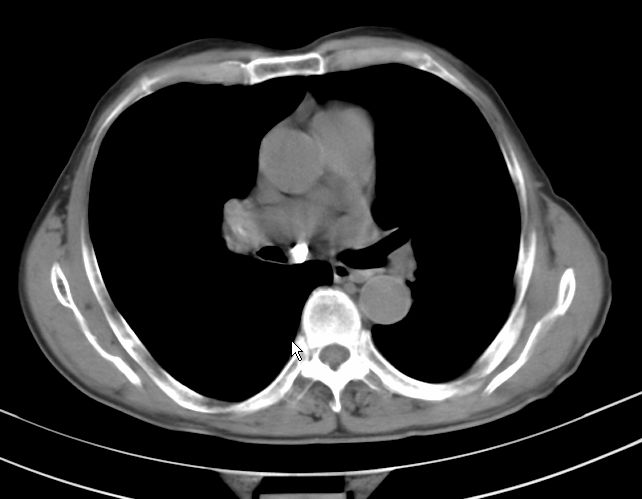

标题: CT17095:胸部病变请大家看看是什么性质的

请大家看看是什么性质的。炎性病变首先考虑哪一种炎症。

支持右肺上叶前段\\下叶内基底段感染,建议抗炎治疗后复查,除外结核.

支持右肺上叶前段\\下叶上段感染,建议抗炎治疗后复查,除外结核.

支持右肺上叶前段、下叶内基底段感染,建议抗炎治疗后复查,除外结核.

右肺上叶前段及下叶内基底段感染性病变;建议抗炎治疗后复查。

楼主说是炎症,凭啥?典型的周围型肺癌(腺癌可能性大),肝内可能已有转移,强化看看吧。